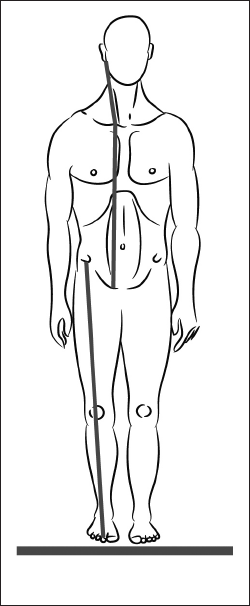

У взрослого человека он постепенно переходит в рефлекс поддержания головы в вертикальном положении, а мышцы-разгибатели формируют заднюю МФЦ (рис. 19).

Рис. 19. Задняя миофасциальная цепь.

Эта цепь позволяет поддерживать тело в вертикальном положении в статике и при ходьбе. Сокращаясь одномоментно, мышцы с одного конца цепи поддерживают баланс мышечной силы на другом.

С последующим развитием нервной системы задняя МФЦ вытягивается и начинается от подошвенной поверхности пальцев стопы.

Если пальцы стоп в ходьбе не участвуют, то сложная координационная мышечная цепь рассыпается на отдельные участки, вызывая избыточное сокращение в отдельных регионах позвоночника и конечностей.

Так возникает нарушение осанки в виде верхне-перекрещенного, нижне-перекрещенного и слоистого синдромов и нестабильность нескольких регионов – в динамике (рис. 20).

Рис. 20. Неоптимальность динамики. Нарушение осанки как результат снижения функции мышц таза.